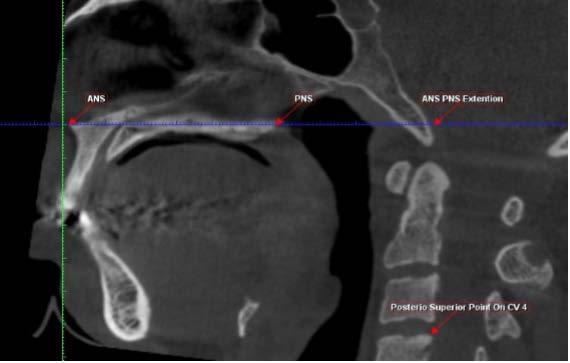

In the explorer view of the software, the image in the coronal section was oriented so that the sagittal slicing plane (Red line) passes through the anterior nasal spine (ANS). This will help to obtain the particular sagittal section which passes exactly through the midsagittal plane. In the sagittal section of the image, the following landmarks were marked (Figure : 1) Then the sagittal image is rotated so that the palatal plane (ANS-PNS) is parallel to that of the axial slicing plane (Blue Line). Since the airway is not bounded fully with hard tissue structures, the anterior and superior boundary is located at the PNS point and the posterior and inferior boundary is located at the C4up point as it corresponds to the deepest point of the vallecula. Taking these landmarks as reference, the external volume of the airway is drawn using a tool provided by the software.